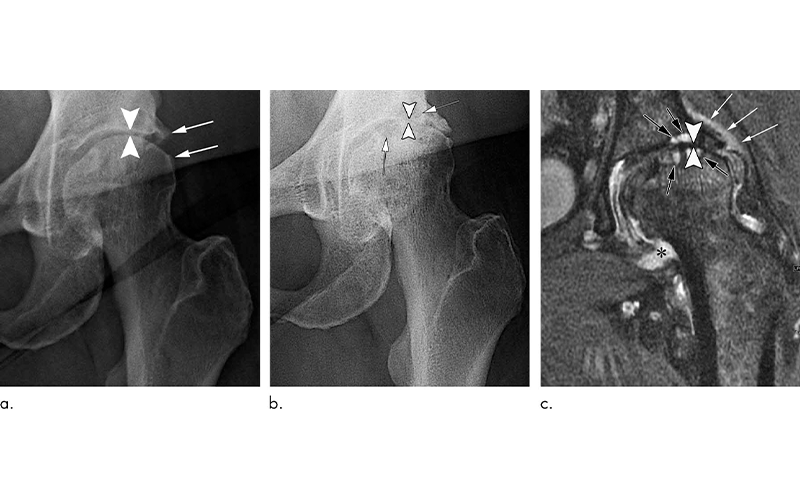

Hip Steroid Injections Associated with Bone Changes

Hip Steroid Injections Associated with Bone Changes Do Steroid Injections Help Hip Arthritis Patients with hip pain may benefit from an injection of steroids into the affected joint, a trial has suggested. They can be used to. Novel intraarticular injections for hip osteoarthritis. Steroid injections can relieve inflammation in the joints, but may have side effects such as bone damage or cartilage thinning. The finding could offer fresh hope for patients with osteoarthritis. Do Steroid Injections Help Hip Arthritis.